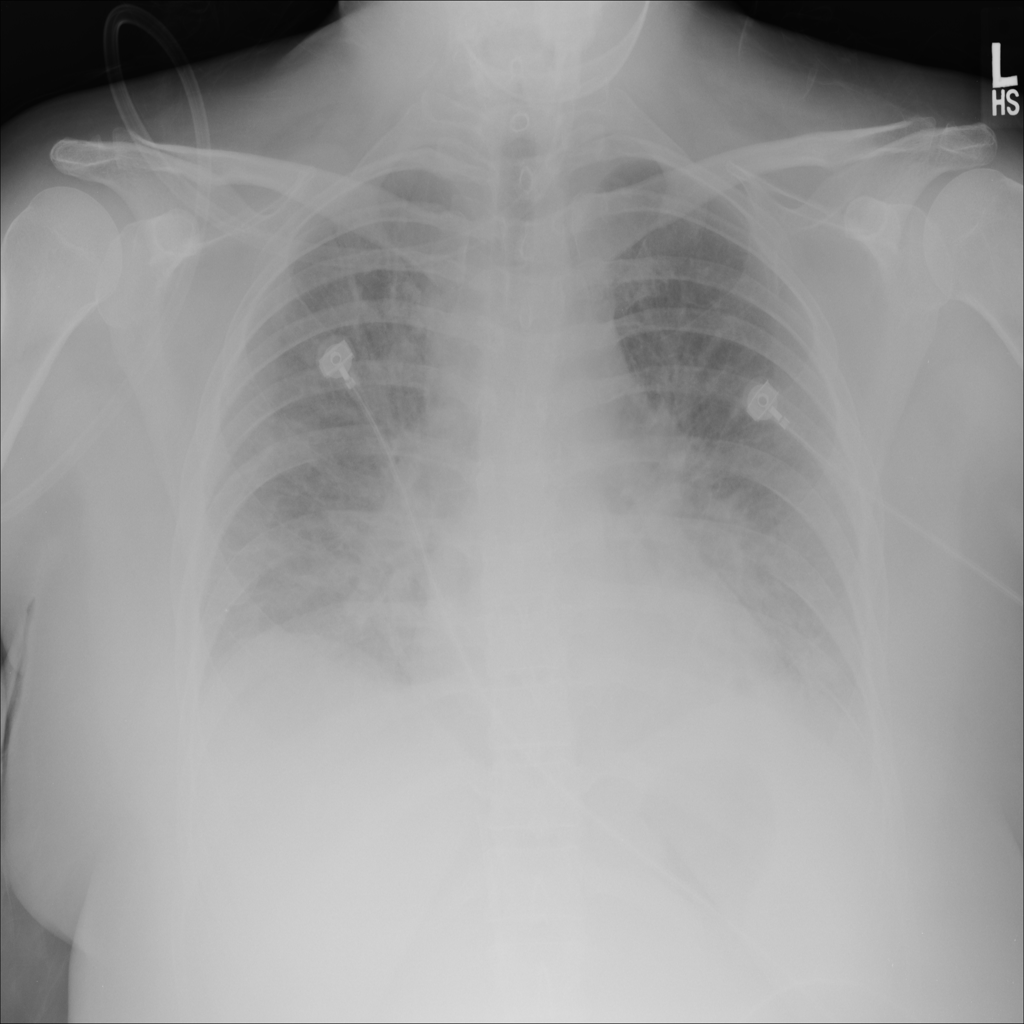

PAT-5B86 · IMG-009Edema

PAT-5B86 · IMG-009

PA